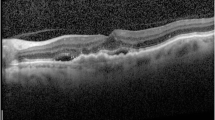

In both models, CAM was able to identify the pathologic region on OCT successfully, based on the generated heat map (Fig. 4). Additionally, in the second model, the learning stabilized faster with transfer learning than with CNN (Fig. 5).

Heat maps for two CNN classification models. a Heat map for the first model for classifying normal and AMD OCT images, b heat map for the second model for classifying the presence or absence of any fluid. CAM was able to identify characteristic areas on the OCT, and it is presented as a heat map. CAM class activation mapping, AMD age-related macular degeneration, CNN convolution neural network, OCT optical coherence tomography